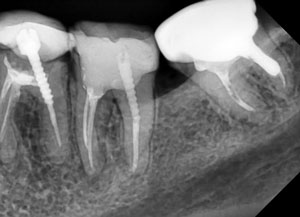

Качество снимков обладает высокой разрешающей способностью отношение сигнал /шум – важнейший фактор в получении изображения, составляет >37 dB, размер пикселя 0,035 мм. Благодаря высокой чувствительности и вариабельности размеров датчиков, визуализация становится детальной, в этой связи возможно проведение диагностики кариеса на контактных поверхностях. Преимущества данной методики при сравнении с пленочной рентгенографии состоит в скорости получения изображения объекта исследования, низкая доза облучения пациентов, возможность постпроцессорской обработки, визуализации деталей в диагностике послеоперационных результатов дентальной имплантации, эндодонтического лечения и постэндодонтического лечения (Рис.5), уточнения расположения кист, гранулем, конкрементов в протоках слюнных желез.

Рис. 5 Диагностика дентальной имплантации и эндодонтичского лечения.